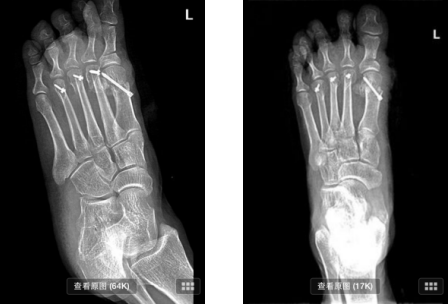

拇外翻畸形是指拇趾在第一跖趾关节处向外侧偏斜移位。拇外翻是一种复杂的解剖畸形,并且在治疗上极具挑战性。拇外翻是累及拇趾的最常见的病变,多见于中老年妇女。

临床表现:①脚部畸形 脚拇趾外翻、跖骨头突出;②疼痛。

呈对称性